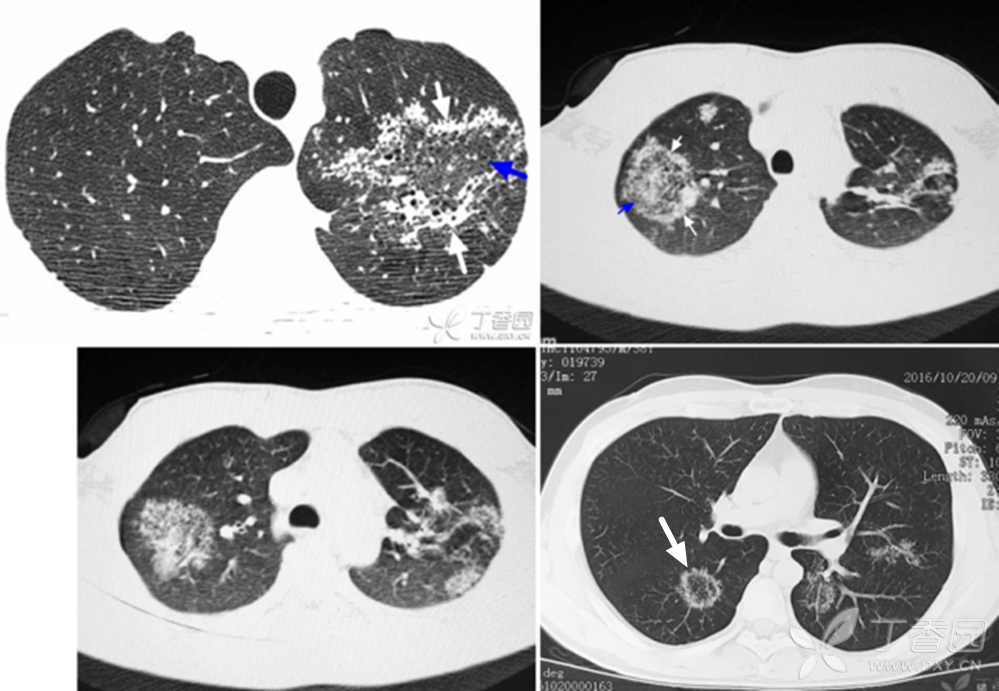

另外两例:反晕征---肺结核.

图片尺寸999x691